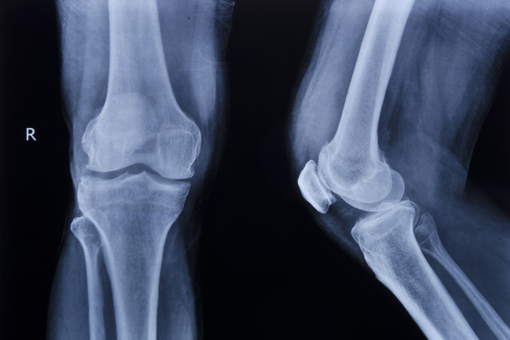

Pubblicato su ARD un lavoro che propone un nuovo modello prognostico, per prevedere l’incidenza di gonartrosi radiografica in 8 anni

E’ stato pubblicato su ARD un lavoro che propone un nuovo modello prognostico, sviluppato e validato esternamente e basato su variabili cliniche comuni e biomarcatori proteici, per prevedere l’incidenza di gonartrosi radiografica (rKOA) in un lasso di tempo pari a 96 mesi (8 anni) in individui senza segni radiografici di malattia. Il nomogramma risultante è uno strumento utile per stratificare le popolazioni ad alto rischio e potrebbe potenzialmente portare a strategie di medicina personalizzata per il trattamento dell’osteoartrosi (OA).

La gonartrosi (KOA) rappresenta una delle malattie reumatologiche più diffuse ed è classificata tra le prime 10 cause di disabilità cronica, con un impatto enorme sulla sanità. L’impossibilità di individuare gli stadi precoci della malattia e la mancanza di trattamenti efficaci lasciano i pazienti affetti da KOA senza opzioni cliniche non chirurgiche. La ricerca, pertanto, si è focalizzata sulla scoperta di marcatori prognostici per identificare gli individui ad alto rischio di sviluppare KOA prima che si manifesti il danno articolare.